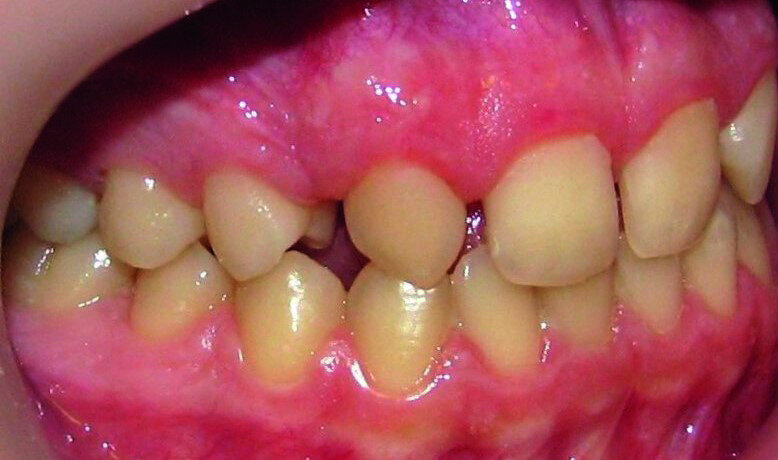

Then occlusal analysis (Figs. 11–21) was performed:

- Skeletal Class III (Fig. 17).

- Dental Class I.

- Maxillary hypoplasia with lower arch dental compensations.

- Insuficient overbite and overjet.

- Upper spacing due to the laterals agenesis (Fig. 18).

- Upper midline deviated to the right.

A 13-year-old patient complaining about the aesthetic aspect of her smile was sent to my office by a general dentist with a diagnosis of the bilateral lateral incisors agenesis.